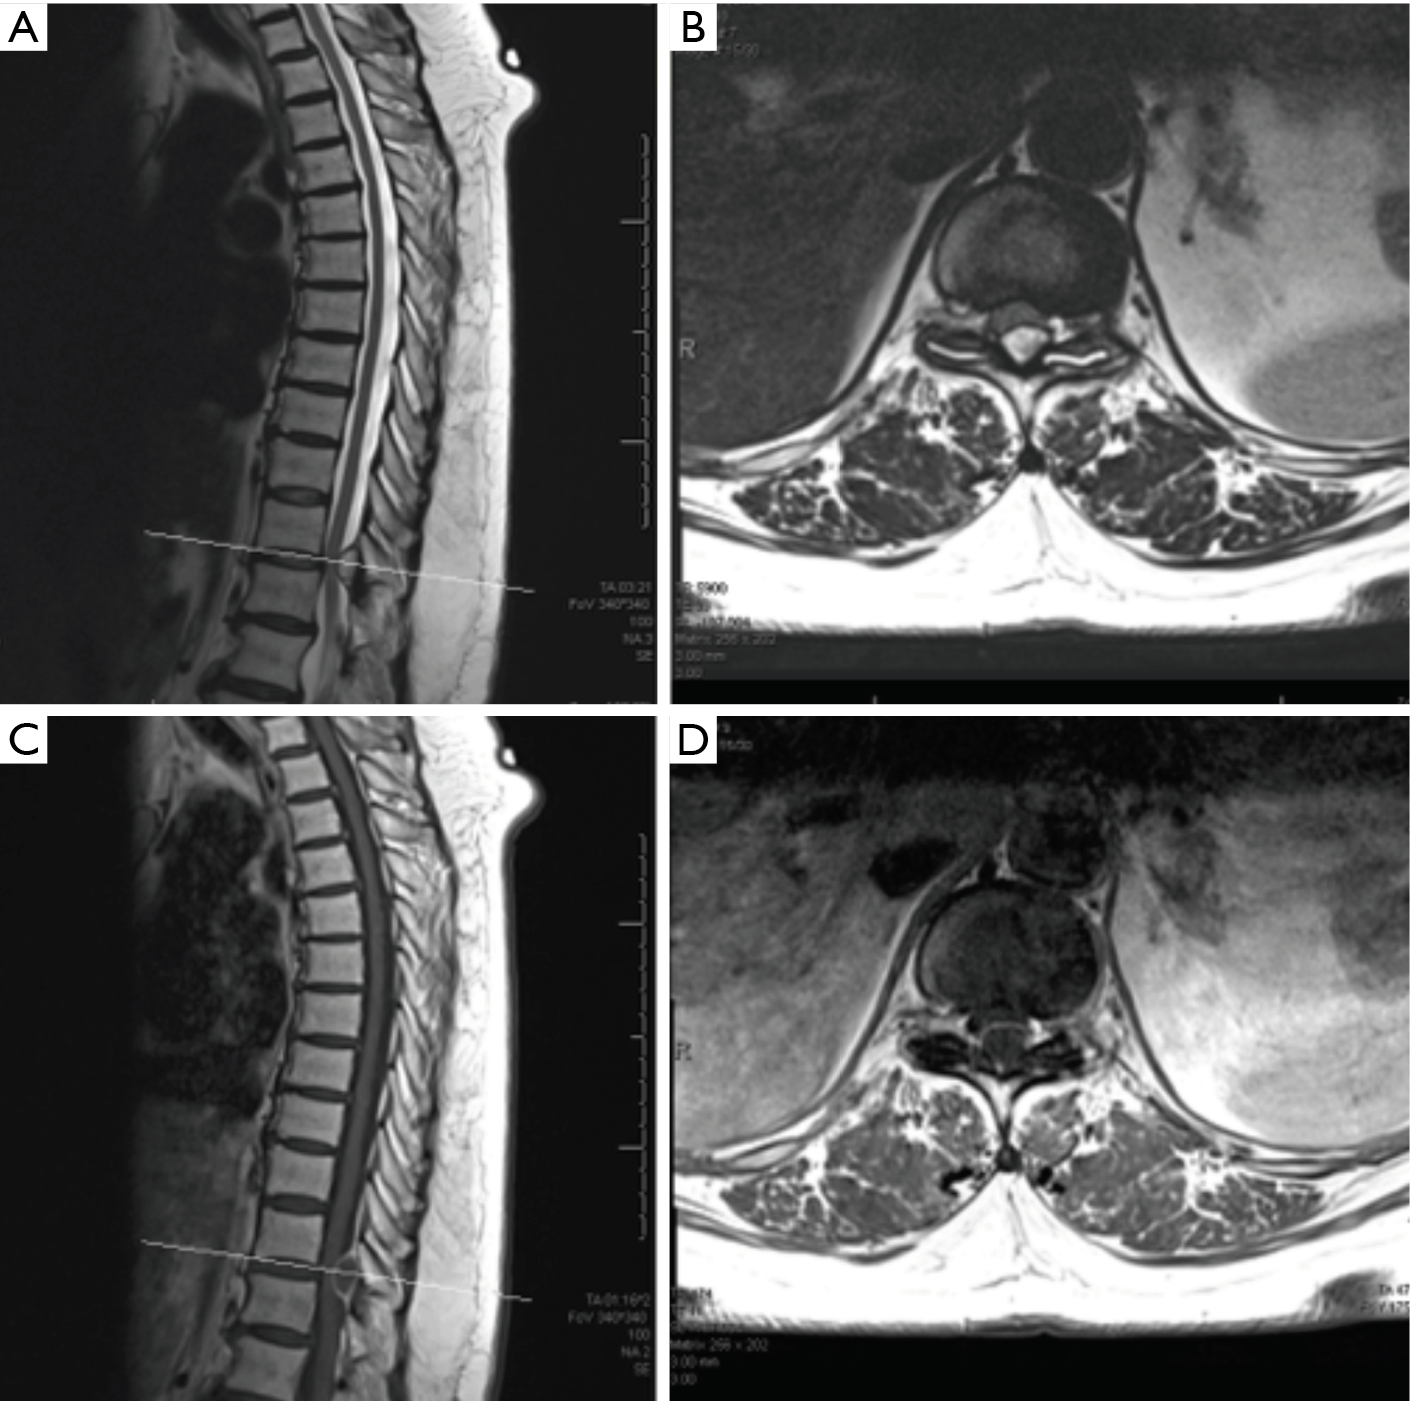

Spinal cysts are a relatively uncommon cause of back pain that often develop as a result of degeneration. Spinal osteoarthritis cannot be reversed, but treatment can slow its progression and control pain. Webmd looks at spinal osteoarthritis, including the causes, symptoms, and treatments of this painful back and neck condition.

Webmd looks at spinal osteoarthritis, including the causes, symptoms, and treatments of this painful back and neck condition. Spinal arthritis is inflammation of the facet joints in the spine or sacroiliac joints between the spine and the pelvis. Does cervical spine nerve lesion have pain on hyperextension and rotation of cervical spine. However, if a spinal arachnoid cyst has not been identified and a patient presents with symptoms associated with the condition, the doctor may order.